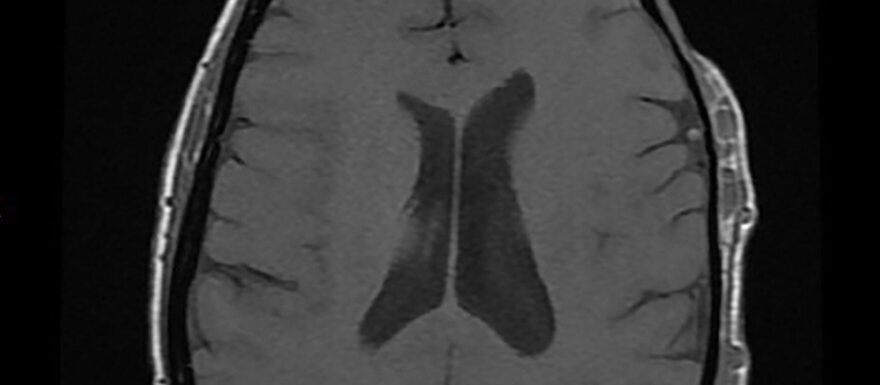

Vasculaire anomalieën beslaan een heterogene groep afwijkingen, variërend van onschuldige cutane laesies tot levensbedreigende malformaties. Incorrect gebruik van terminologie heeft van oudsher tot veel verwarring in de klinische praktijk en onjuiste diagnoses geleid. Tegenwoordig wordt het ISSVA-classificatiesysteem gebruikt als gouden standaard voor vasculaire anomalieën. Hierin worden twee hoofdcategorieën onderscheiden: vasculaire tumoren (zoals hemangiomen) en vasculaire malformaties. In dit artikel wordt ingegaan op de ISSVA-classificatie en de belangrijkste verschillen tussen de categorieën. Ook wordt uitgebreid ingegaan op de radiologische beeldvorming, waarbij met name echografie en MRI een grote rol spelen. Tot slot wordt een overzicht gegeven van de belangrijkste therapieën van vasculaire malformaties, met de focus op interventieradiologische behandelingen.